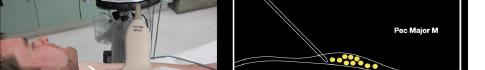

At this point, the pectoralis major and minor muscles can be visualized. By rotating the transducer 45 degrees clockwise, the thoracoacromial artery can be identified between the pectoralis major and minor muscles. Also, the serratus anterior muscle should be identified resting just above the anechoic rib (Image 2).

major and minor muscles. Hydrodissection with normal saline will confirm opening of the correct fascial plane (Image 3). Anesthetic can then be gently and slowly deposited in 2-3 milliliters (mL) aliquots to a recommended amount of 15 mL per Pecs block. It is imperative to calculate your weight-based recommended dosage of anesthetic beforehand as to prevent local anesthetic systemic toxicity (LAST). If dilution is needed, the injectate can be mixed with sterile 0.9% normal

Image 1. Initial probe placement for the pectoralis nerve block I and II illustrated on a model: the blue line indicates transducer, and the green dot indicates directional marker corresponding to ultrasound image. Image 2. Final probe placement prior to the pectoralis nerve block I and II: blue line indicates transducer, and green dot indicates directional marker corresponding to ultrasound image.

Image 3. Pectoralis nerve block I injection between the pectoralis major and minor muscles: arrow on patient model indicates needle direction; the green dot indicates directional marker, and yellow dots indicate injectate within the fascial plane. Image 4. Pectoralis nerve block II injection between the pectoralis minor and serratus anterior muscles: the arrow on patient model indicates needle direction; the green dot indicates directional marker; and yellow dots indicate injectate within the fascial plane.